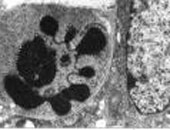

Andreas Villunger vom Institut für Pathophysiologie und seine Kooperationspartner in Melbourne konnten nachweisen, dass zwei Proteine, die den Zelltod fördern, eine wesentliche Rolle bei der Behandlung gewisser Tumore spielen. Sie erhoffen sich dadurch neue Erkenntnisse für die Krebsbehandlung. Ihre Ergebnisse wurden im Science veröffentlicht.

In der soeben unter dem Titel "p-53 and Drug-Induced Apoptotic Responses Mediated by BH3-Only Proteins Puma and Noxa" erschienenen Arbeit in der Fachzeitschrift Science konnte das Forscherteam gemeinsam mit Kooperationspartnern in Melbourne zeigen, dass zwei zelltod-fördernde Proteine der Bcl-2 Familie (genannt PUMA/bbc3 und NOXA) kritisch für die apoptotische Wirkung von gängigen Zytostatika und der Strahlenbehandlung sind. Lymphozyten und Fibroblasten von Mäusen, denen diese Proteine fehlen, zeigen eine drastisch verringerte Sensitivität gegenüber Gammastrahlung, Zytostatika- aber auch Steroidbehandlung. Es wäre somit denkbar, dass das Fehlen dieser Proteine mit einem schlechten Ansprechen von gewissen Tumoren auf Behandlung korreliert. Die Wissenschaftler überlegen daher, ob diese Proteine als prognostische Marker herangezogen werden können. Weiters wäre es denkbar, dass das Fehlen dieser Protein die Entstehung von bösartigen Erkrankungen erleichtern, beschleunigen oder gar erst ermöglichen könnte - eine Theorie, die die Wissenschaftler als nächsten Schritt überprüfen werden.(sp)